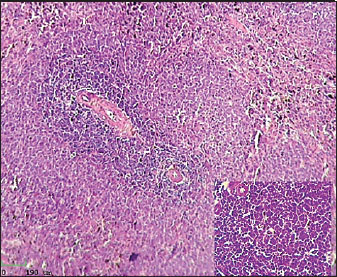

Histological analysis of spleen

Histological examination of the splenic tissue of rats treated with L-arginine showed notable pathological alterations. These included: Congestion of blood vessels within both the red and white pulp and lymphoid hyperplasia in the white pulp, indicating increased proliferation of lymphoid cells, suggestive of immune stimulation or chronic inflammation (Fig. 4). In contrast, the spleen from control male rats exhibited normal histological architecture. The white pulp and red pulp regions were clearly distinguishable. Central arteries and blood vessels appeared unremarkable, and no signs of congestion, inflammation, or hyperplasia were observed. The lymphoid follicles within the white pulp were of normal size and density (Fig. 3)

Fig. 3. Histological section of male rat spleen of control group, stained with Hematoxylin and Eosin (H&E), showing villus structure at 10x magnification using light microscopy.

Fig. 4. Histological section of male rat spleen treated with L-arginine, stained with Hematoxylin and Eosin (H&E), showing villus structure at 10x magnification using light microscopy.

Lymphoid hyperplasia of the spleen is when there are more lymphocytes than usual. It usually happens because of an inflammatory or immune response. This finding usually means that the immune system is working harder or longer in the spleen, which shows that the immune system is still controlling the body as a whole. This kind of hypertrophy is a sign of an active immune system or long-term inflammation (Hobbie et al., 2024).

During enteritis, the spleen is an important part of the immune system because it filters the blood and is where immune cells first become active. According to Mebius and Kraal (2005). There is a white pulp in the spleen that helps activate and multiply lymphocytes. This makes it possible for adaptive immune reactions to work together. In the context of enteritis, inflammation in the intestines can cause microbial products and inflammatory chemicals to move into the bloodstream. The spleen is very important for getting rid of these substances and keeping the defense system working as a whole. This shows how important the spleen is for keeping the immune system in balance during times of inflammation in the gut. It also helps control inflammation outside of the gut and stops infections from spreading.